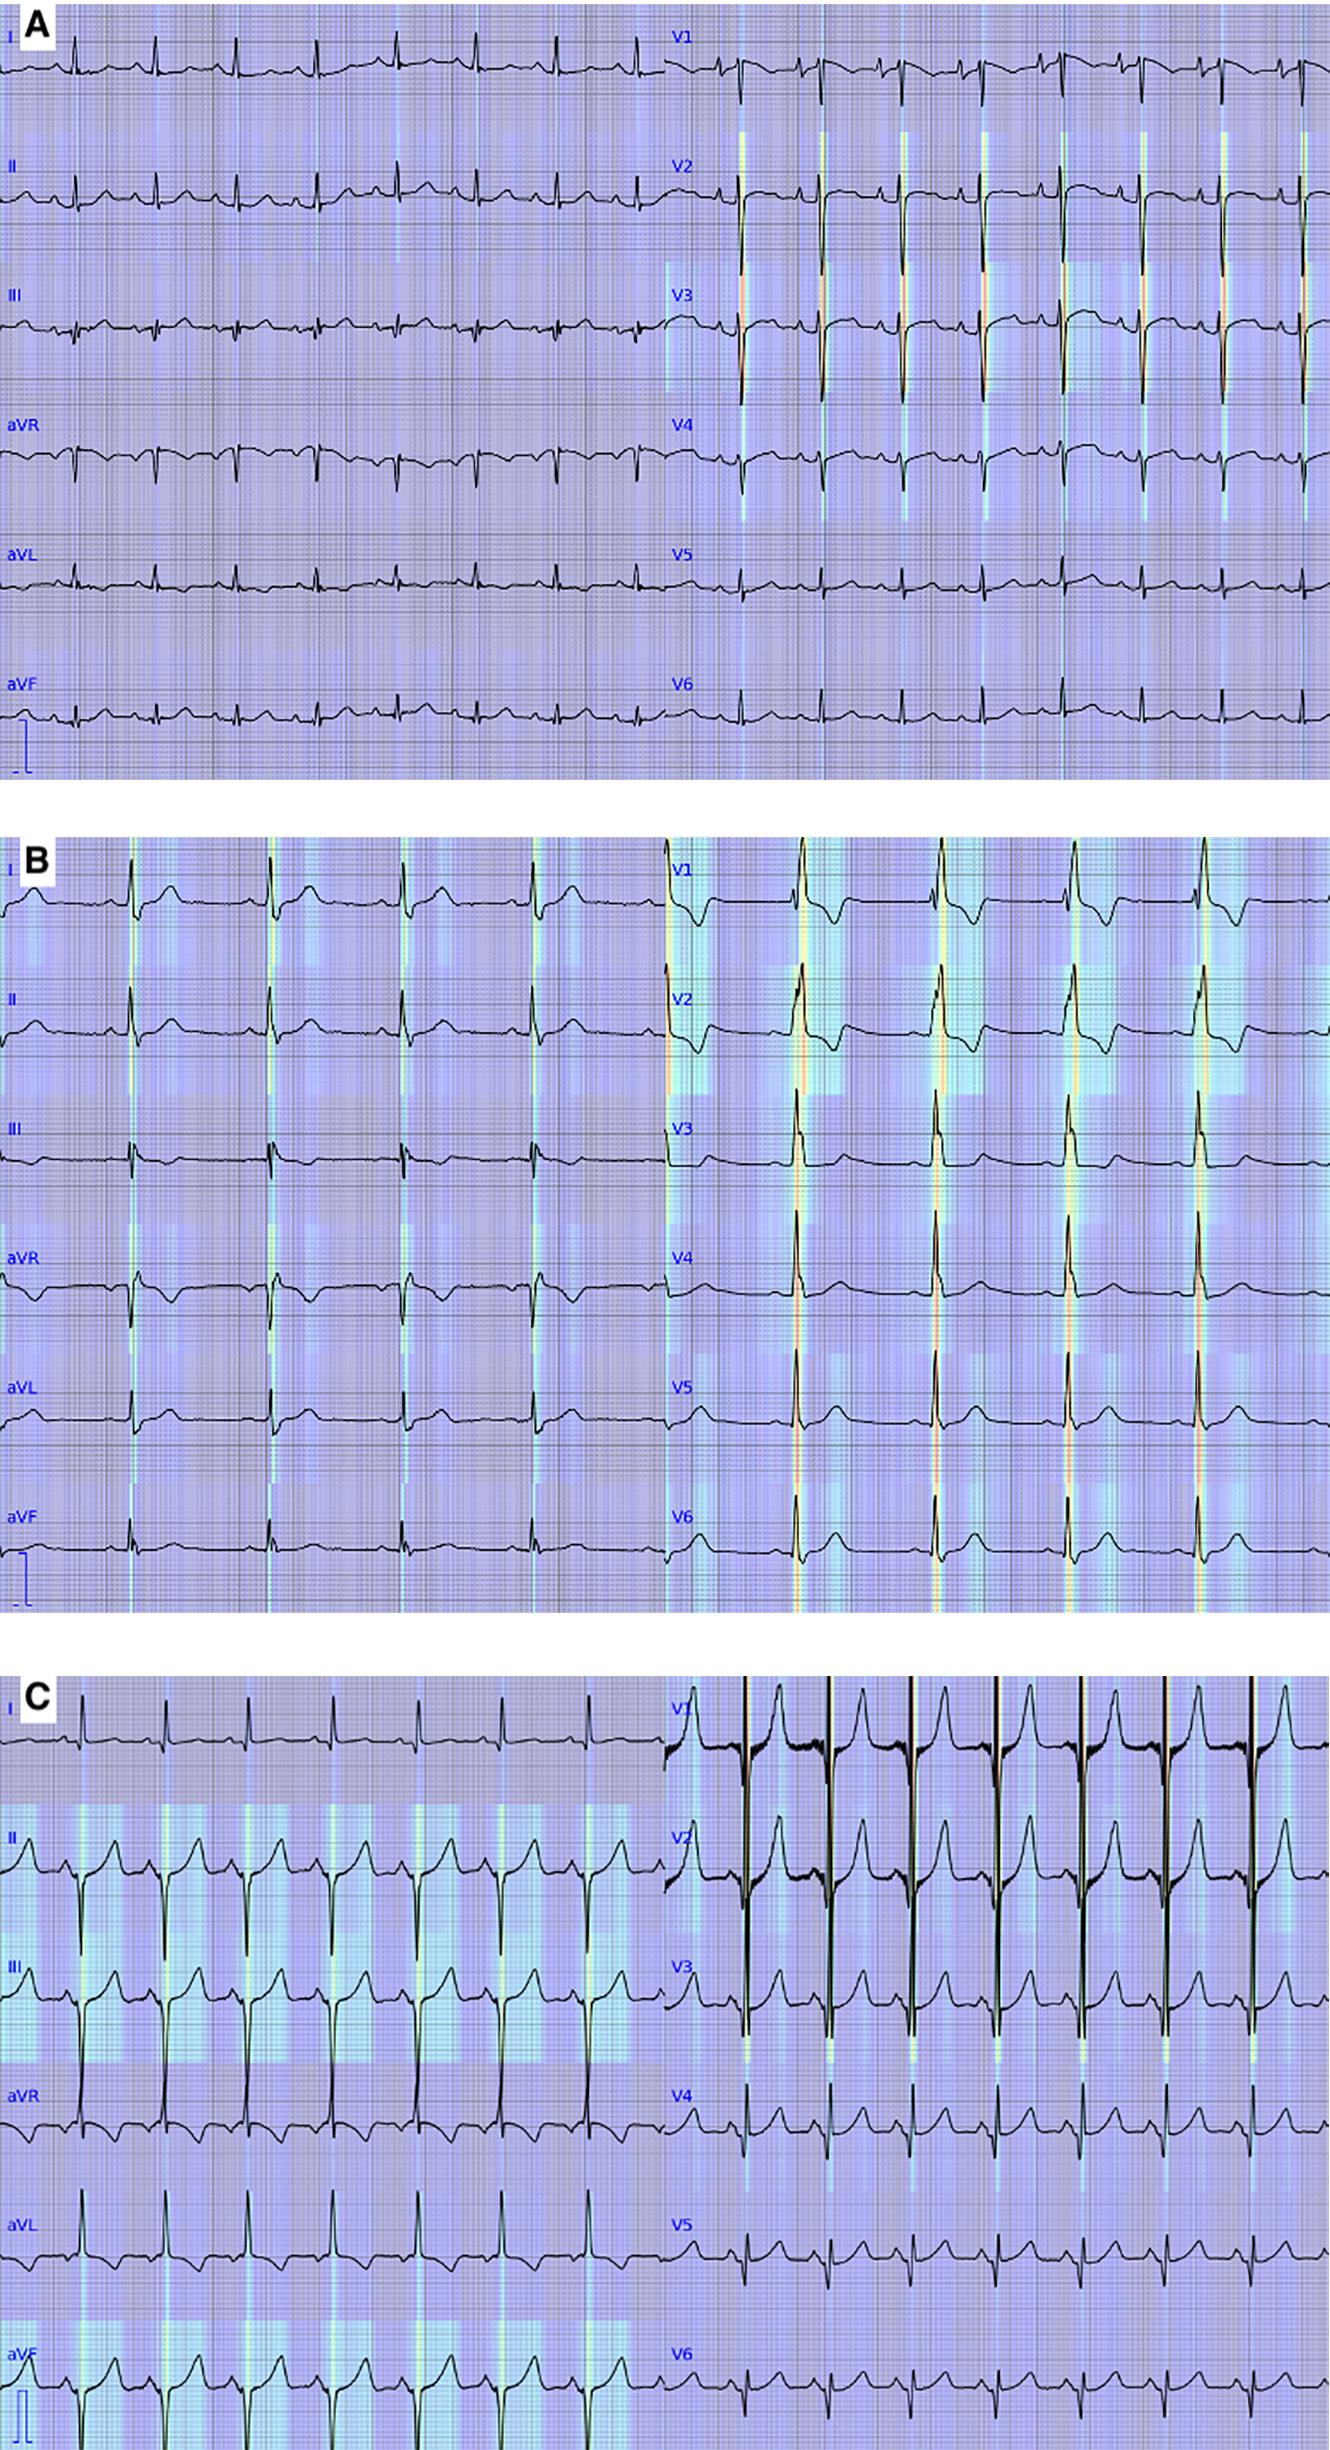

Interpretation for ECGs with ST-T abnormality, with complete right bundle branch block, and with QRS axis abnormality, right ventricular hypertrophy, and ST-T abnormality by our model was visualized and shown in Figure 7.

Figure 7

Visualization of the deep learning-based model. Red and yellow represent areas where the model focused on to output predictions. (A) An electrocardiogram with ST-T abnormality. (B) An electrocardiogram with complete right bundle branch block. (C) An electrocardiogram with QRS axis abnormality, right ventricular hypertrophy, and ST-T abnormality.

One of the disadvantages of a deep learning-based model for clinical purposes is that the recognition and interpretation of a model are not well explained, and it is often considered a “black box.” In this study, we showed areas of ECG wave on which our deep learning-based model focused on to output prediction, as shown in Figure 7. The areas were generally consistent with the abnormalities in the abnormal ECGs except for the one with ST-T abnormality. The inconsistency in the ECG with ST-T abnormality may be caused by the frequent association of ST-T abnormality with the other abnormalities in the training data. This visualization technique may help clinicians review the model's predictions.